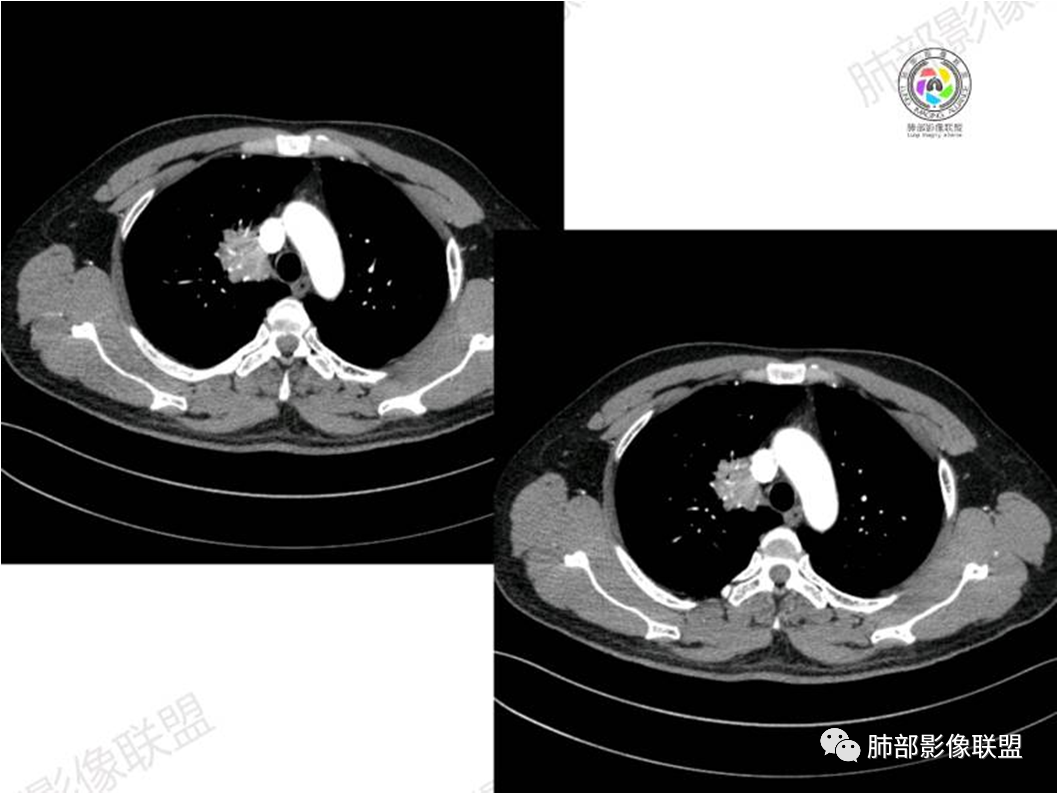

胸部CT:

南边:

病灶紧贴纵隔胸膜

糊墙,胸膜外未见明显侵犯迹象

病灶整体狭长一些

边缘平直、凹陷为主

支气管外侧带的通畅,片内侧带的似乎中近端狭窄,堵塞

内部肺动脉走形还可以

近端支气管壁弥漫增厚

强化均匀

整体炎性的特点比较明显

不踏实的地方:

边上有些毛糙

恶性待排除

恶性:还是淋巴瘤多见一些。